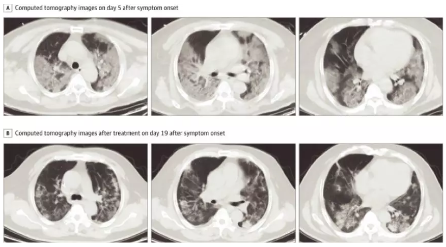

胸部CT扫描显示所有患者的肺部都有斑片状影或磨玻璃样影。